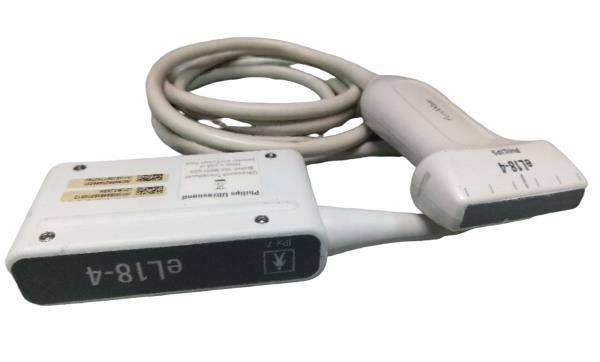

The CE Digital Laptop Ultrasound Machine offers outstanding imaging capabilities that are essential for modern diagnostic practices. It features a 6.5MHz Transvaginal probe that provides high-resolution images, enabling healthcare professionals to visualize internal structures with great clarity. This machine is designed to help in various examinations, ensuring better accuracy and improved patient care.